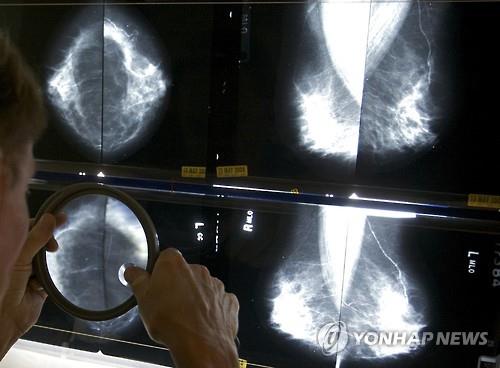

(서울=연합뉴스) 최평천 기자 = 골다공증 치료제가 폐경기 여성의 유방암 재발률과 사망률을 낮춰준다는 연구결과가 나왔다고 영국 일간 가디언 등이 24일(현지시간) 보도했다.

영국 의학저널 랜싯 최신호에 실린 셰필드암연구센터의 논문에 따르면 골다공증 치료제인 비스포스포네이트 제제가 유방암 재발률을 28% 줄일 뿐만 아니라 유방암 진단 후 10년 동안의 사망률도 18% 감소시키는 것으로 확인됐다.